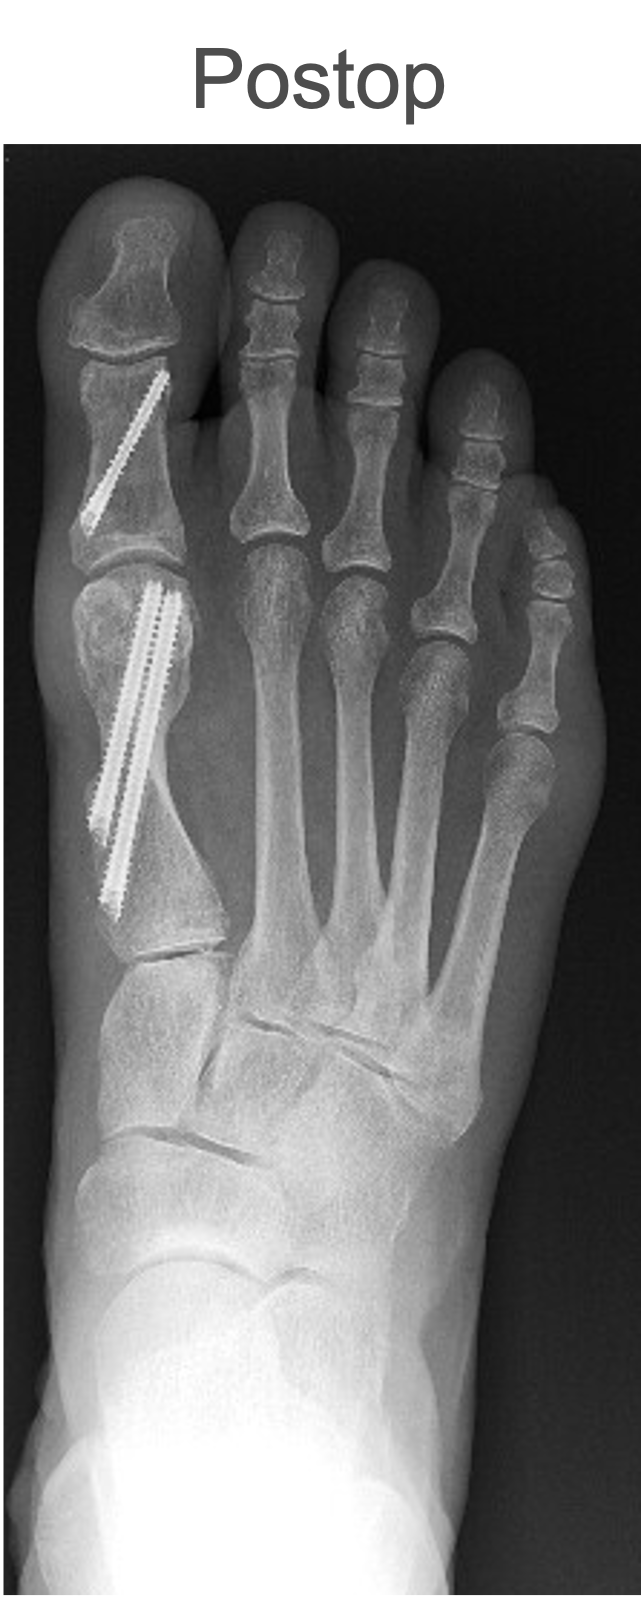

Pecaplasty Percutaneous Bunion Correction and Targeting Guide System (Novastep) allows for simple, precise, and reproducible percutaneous bunion correction using a targeting guide to help the surgeon control translation of the metatarsal head and accurately place K-wires. The system then uses Peca screws to fixate and stabilize the correction, says Novastep.

The company shares the easy positioning of the targeting guide on the foot, with the paddle beneath the medial capsule, after a transverse osteotomy of the first metatarsal. They go on to say that the stabilization sleeve guides the traction wire into the metatarsal canal before metatarsal head translation. Then, the surgeon adjusts the targeting arc to allow K-wire insertion.

Bradley Abicht, DPM, FACFAS finds that over 18 months of using this jig-guided system he has noted reproducible deformity correction and appropriate placement of internal fixation.

“It was the first of its kind,” he adds. “The PECA procedure (or percutaneous bunion correction) demonstrates a high learning curve, and thus the jig was developed to aid surgeons in reproducible internal fixation placement and cut down the learning curve.”

Dr. Abicht shares that he feels minimally invasive procedures, like that afforded by the innovations in Pecaplasty, are continuing to evolve and grow in the surgical world.